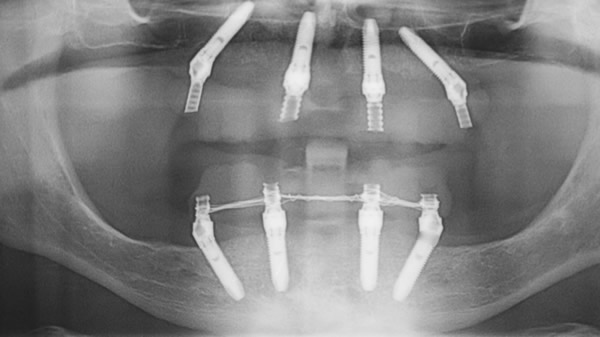

“All on Four” è una tecnica impiantistica dentale che consiste nel posizionamento di quattro impianti sull’arcata dentale che, disposti in posizione strategica nella parte anteriore della mandibola, sono in grado di sostenere il carico immediato di una protesi provvisoria da 10-12 corone.

La “All on Four” prevede l’utilizzo di impianti dentali inclinati, detti Tilted, grazie ai quali è possibile evitare innesti ossei complessi dal punto di vista biologico e che avrebbero costi eccessivi per i pazienti, inserendo nell’osso residuo impianti dentali lunghi.

Innazitutto vengono posizionati i quattro impianti. Su di essi viene poi applicata una protesi acrilica temporanea da 10 a 12 corone, sufficienti a ricoprire l’intera arcata dentale.